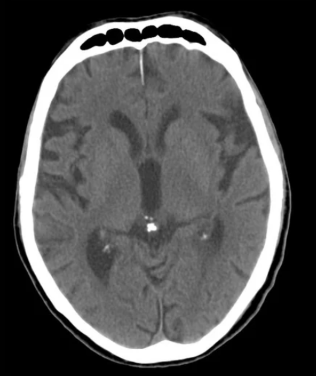

Q: How do I know if my pineal gland is calcified?

A: Most people's pineal glands show some degree of calcification by middle age. Signs include: disrupted sleep patterns, difficulty achieving deep sleep, loss of dream recall, feeling disconnected from intuition, circadian rhythm disturbances (jet lag sensitivity, shift work intolerance), and early aging signs. An MRI or CT scan can show calcification directly, though most doctors don't routinely check for it.

normal pineal gland

calcification of the pineal gland